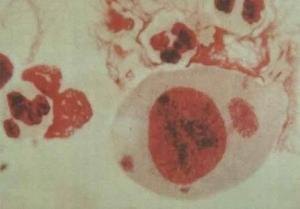

1935年宫川氏等从病灶局部取材涂片检查,以及从实验动物的猴脑、脊髓、睾丸及淋巴结中抽出液体涂片做姬姆萨染色,均发现深天蓝色小体,称为宫川小体。 60年代通过电子显微镜观察及细胞培养法对本病病原体进行研究,结果证明此 小体与 沙眼、鹦鹉热的病原体的性状有相似之处,与典型的病毒则不同,被命 名为衣原体。本衣原体在人体外比较稳定,能保持生活力2—3日,在去氯 自来水中至少能活5日,50℃30分钟或95—100℃1分钟均可被灭活。紫外线、干燥、75%酒精、2%来苏水和2%氯胺可杀灭。对广谱抗生素和磺胺制剂敏感,对青霉 素和氨苄青霉素稍敏感,对链霉素、庆大霉素及呋喃西林等耐药。现已查明本 病衣原体是 沙眼衣原体的一个亚群,属血清型沙眼衣原体(L1—L3型),目前 已称为性病淋巴肉芽肿衣原体。